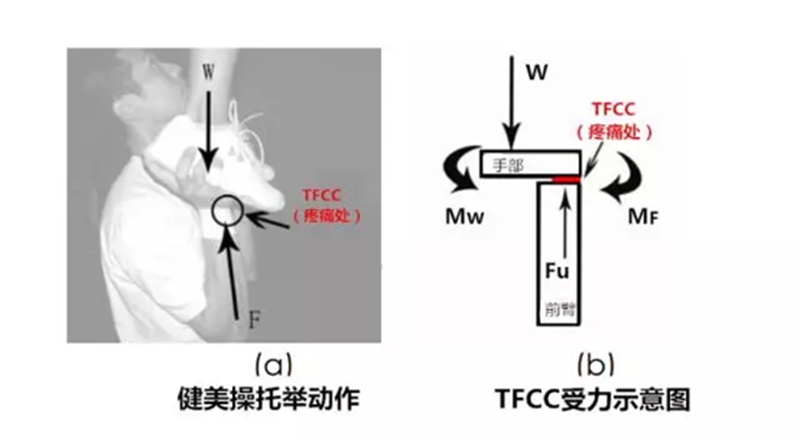

TFCC Load Test:患者坐位,检查者一只手握住患者的前臂,另一只手握住患者手部,然后沿着中轴施加力量并将手腕向尺侧偏移,同时将手腕往背侧和掌侧移动或旋转前臂。如果此测试会引起TFCC处疼痛感、有喀、啪声则测试为阳性。

图 TFCC Load Test